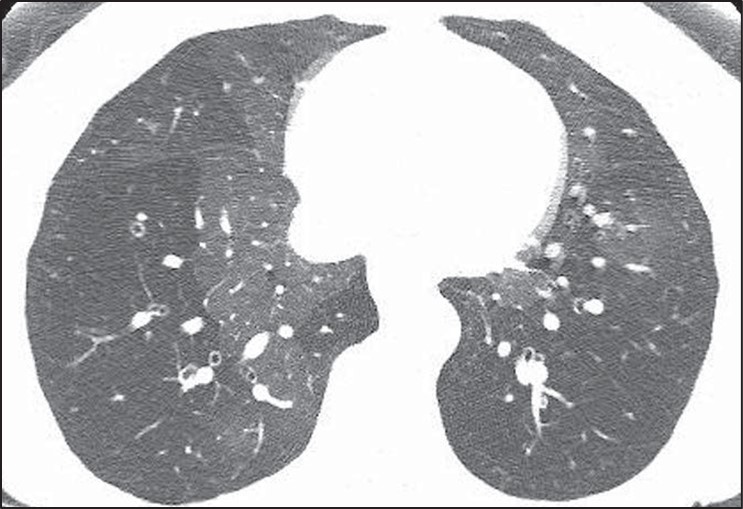

Honeycombing can be confidently diagnosed when there is a group of round clustered air-filled cysts in a row or cluster in the subpleural lung [5]. The subpleural involvement in honeycombing is critical in distinguishing it from other abnormalities. Multiple layers of cysts increase the reader’s confidence in honeycombing but are not required for diagnosis. Honeycomb cysts usually range in size from 3 to 10 mm and have relatively thick, well-defined walls [6]. In general, there is moderate agreement among radiologists for the presence of honeycombing, with kappa values ranging from 0.4 to 0.6 in one series comparing 43 different observers. There was disagreement on the presence of honeycombing in 29% of these cases [7]. Use of the above general rules for the features of honeycombing is helpful when distinguishing from common mimics. The most frequent findings mistaken for honeycombing include traction bronchiectasis, cystic lung disease, emphysema, and subpleural reticulation [8].To distinguish traction bronchiectasis from honeycombing, the shape of the air-filled structure should be noted. Airways in traction bronchiectasis are tubular in shape, which may be best seen on multiplanar reformatted images. Additionally, air-filled structures in the central or peribronchovascular lung are not consistent with honeycombing and are very likely a result of dilated airways (Fig. 2).

Fig. 2—Patient with scleroderma and fibrotic nonspecific interstitial pneumonia. Left, HRCT scan shows traction bronchiectasis mimicking honeycombing. Right, HRCT scan shows that air-filled structures spare subpleural lung.